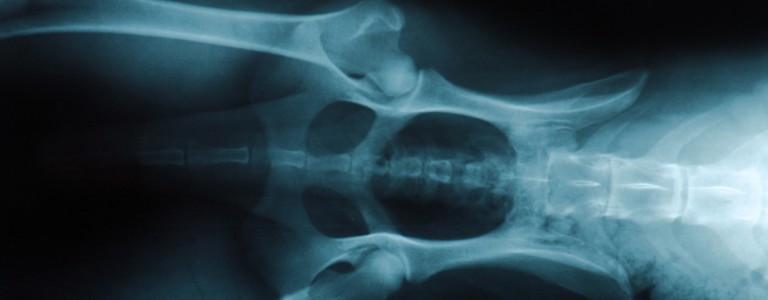

Si vous suspectez que votre chien souffre d'arthrose, un vétérinaire pourra en confirmer le diagnostic grâce à votre description des symptômes, un examen clinique complet et des examens d’imagerie.

Chirurgie

En fonction de la cause initiale de la maladie, une chirurgie peut être envisagée, notamment dans le cas de dysplasie de la hanche